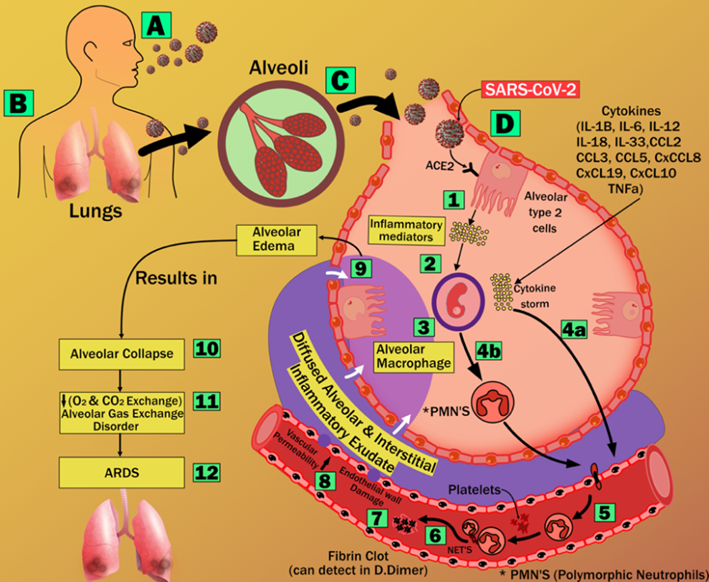

COVID19 is a highly transmittable and pathogenic viral infection that is caused by severe acute respiratory syndrome coronavirus 2 (SARS-CoV-2) [237]). It has led to a dramatic loss (nearly infecting ~155 Million and perishing ~3.3 Million people as of 5th May 2021) of life worldwide [238].

Several studies have suggested that COVID-19 severely affects the lungs of an individual and has adverse effects on other organs of the body [239]. It is seen that the increased mortality due to SARS-CoV-2 is mainly due to viral pneumonia induced Acute Respiratory Distress Syndrome (ARDS) [240]. ARDS leads to lung damage (refer to Appendix Fig. 14). SARS-CoV-2 enters the lungs via aerosol transmission, which further attaches to the host cells. This leads to respiratory symptoms that can be categorized as the earliest clinical presentation of COVID-19 [44].

Imaging has shown to be very useful in understanding COVID-19 severity [241, 242]. Comorbidity has been shown to affect the lungs and heart more aggressively [45, 46, 49]. SARS-CoV-2 causes brain and heart injuries via different pathways (as seen in Fig. 11).

Trends have shown a worsening of cardiac events in COVID-19 patients with underlying conditions such as coronary artery disease, hypertension, and diabetes mellitus [266]. Many reports from admitted patients have also suggested cardiac injury in about 12% to 26% of them. This exists due to the presence of pericytes in the heart, which have a high expression of ACE2 that are the same receptors through which the virus gains entry into the cells of the body. The cytokine released during the infection could affect the intramural coronary vessels of the patients. It is also seen that cardiovascular diseases have a major effect on ARDS in patients with COVID-19 affected lungs [239].

Some studies also suggest that abnormal immune system response is likely to be the underlying cause of myocardial injury during coronavirus infection. Thus, it is suggested that potential cardiac involvement should be identified early to provide a prompt diagnosis for improving the outcome [45]. It is noted that the consequences of dysregulation of the renin-angiotensin system caused by SARS-CoV-2 inside atherosclerotic plaques lead to endothelial dysfunction. This progresses into thrombosis, which in turn favours the invasion of plaque by inflammatory cells. These events may transform vulnerable plaque into a complicated and ruptured plaque [267]. Some studies also suggest that if positive for SARS-CoV-2 and asymptomatic, patients could be at increased risk of developing cerebral ischemic strokes, and myocardial infarction due to increased instability of coronary and carotid plaques [49, 268].

As mentioned above COVID-19 patients develop several complications, among these is the elevated level of IL-6 (interleukin-6). It is responsible for signalling the liver to increase the synthesis and secretion of C-reactive protein (CRP) levels [269]. Higher CRP levels in the blood are diagnostic of extensive tissue damage and pathological inflammatory response. It was observed that at the early stage of COVID-19, CRP levels were positively correlated with the diameter of lung lesions and the severity of COVID-19 [270]. Moreover, CRP levels can be measured and used as a lab-based blood biomarker, which is a simple, affordable, and rapid way to assist the therapeutic conditions and to evaluate the severity of the disease [269]. Thus, CRP levels are also seen to be an effective diagnostic tool in measuring the severity of COVID-19. Anti-inflammatory agents helped in suppressing the elevated levels of IL-6, thus keeping CRP levels in check. In patients with CVD risk, a high burden of subclinical inflammation is associated with COVID-19 development of subclinical disorders or cause cardiovascular damage [271]. However, nonsteroidal anti-inflammatory drugs (NSAID) should be avoided in patients with a high risk of cardiovascular disease as they are seen to increase the risk of heart attack, stroke and high blood pressure [272, 273]. Generally, ACE2 plays an important role in the cellular entry of SARS-CoV2. Additionally, it also affects the renin-angiotensin-aldosterone system (RAAS), which acts as a central mechanism of many drugs including NSAIDs [B7]. An important study also shows the increase of expression of ACE2 levels on heart tissue of diabetic rats after treating with NSAIDs [274].